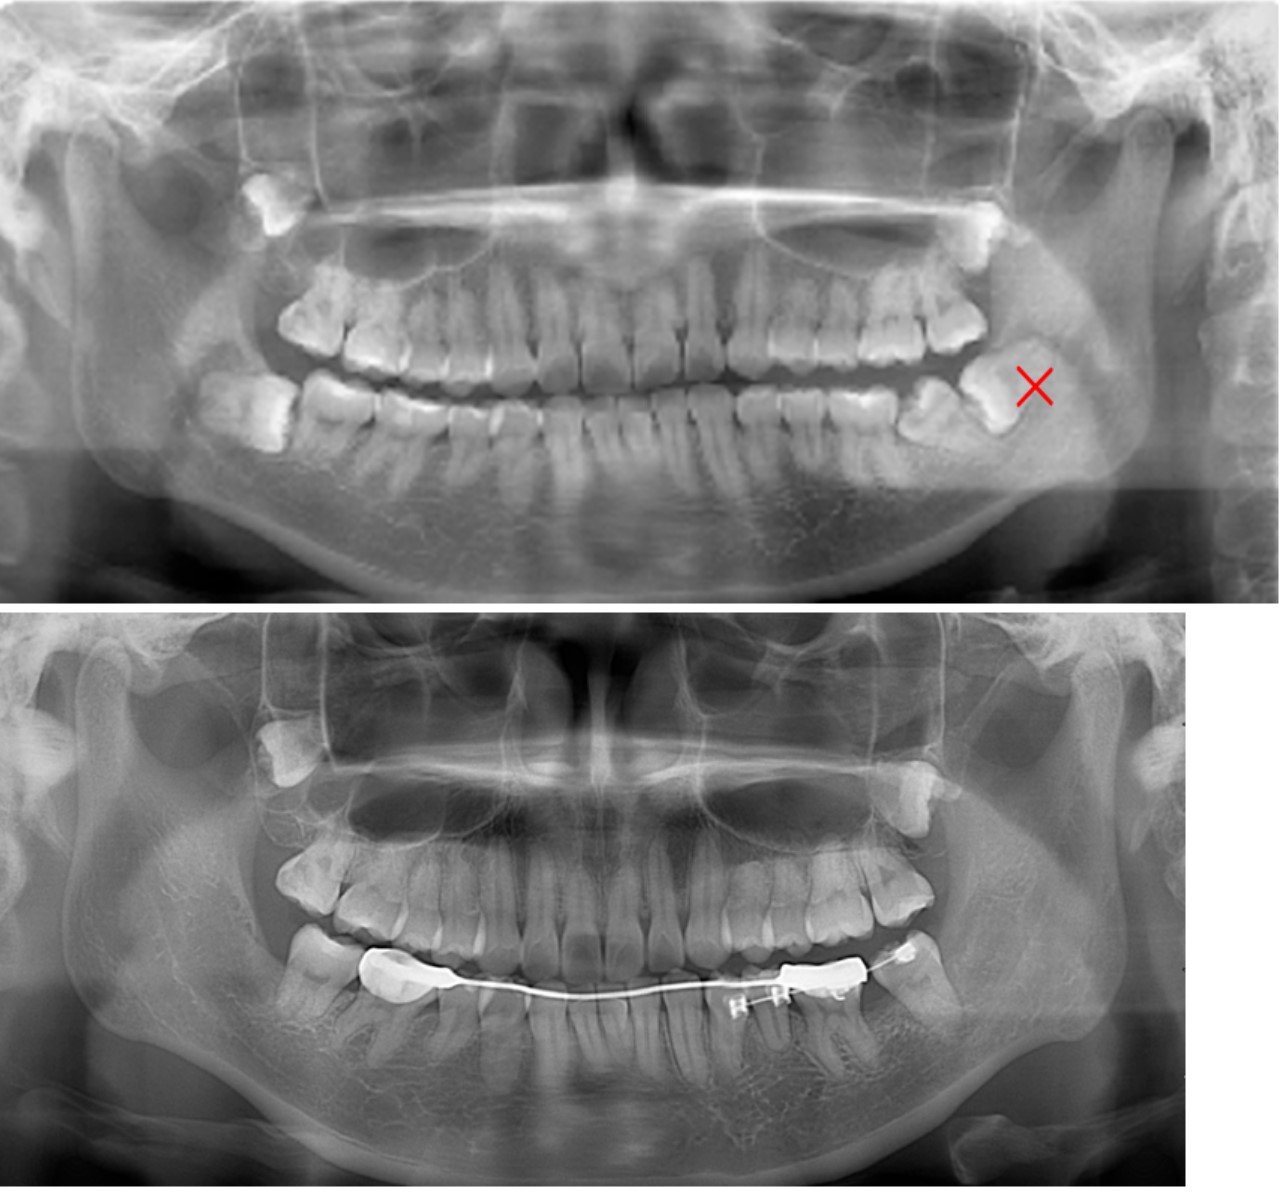

比如有些患者的下颌智齿是近中埋伏阻生的,抵在前面大牙的牙根上,并且智齿的根尖离下颌神经管较近。那么在拔除智齿时存在损伤下颌神经的风险,导致下唇麻木,前面大牙在智齿拔除后松动敏感的风险也较高。如果这个患者需要拔除前磨牙来矫正,并且前牙后移不需要一颗前磨牙的宽度,那么后牙可以适当前移,增加智齿的萌出空间。如图可见在正畸之后,左下智齿近中移动,牙长轴方向有所直立,根尖距离神经管的距离增加,智齿前方牙齿的远中牙槽骨水平也有所增加。此时,正畸后拔除智齿可能导致的神经损伤和前牙松动的风险能明显降低。如图的右上智齿在正畸前拔除需要切开牙龈,拔除后需要缝合,正畸后则可直接拔除。

注:图片都源于冯梦绮医生矫治患者曲面断层片